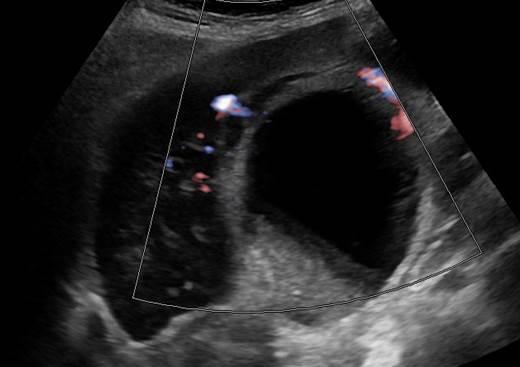

Viêm túi mật

Viêm túi mật - Ảnh 2

» Thông tin: Nữ giới – 88 tuổi.

» Lâm sàng: Đau mạn sườn phải / Sốt.